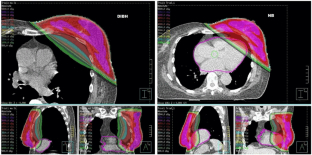

Fig. 1

Adjuvant radiotherapy after breast-conserving surgery (BCS) for breast cancer (BC) is a well-established indication. The risk of ischaemic heart disease after radiotherapy for BC increases linearly with the heart mean dose with no apparent threshold. Radiotherapy to the left breast in deep inspiration breath-hold (DIBH) reduces the dose to the heart. A new linac system with an integrated surface scanner (SS) for DIBH treatments was recently installed in our department. We tested it for potential benefits, safety, patients’ acceptance/compliance and associated additional workload.

Twenty consecutive patients following BCS for breast carcinoma of the left side were enrolled in our institutional DIBH protocol. We compared dose to the heart and ipsilateral lung (IL) between plans in DIBH and free breathing (FB) using standard defined parameters: mean dose, maximal dose to a volume of 2 cm3 (D2 cm 3), volume receiving ≥ 5 Gy (V5), 10 Gy (V10), 15 Gy (V15) and 20 Gy (V20). Comparison of median calculated dose values was performed using a two-tailed Wilcoxon signed rank test.

DIBH was associated with a statistically significant reduction (p < 0.001) in all studied parameters for the heart and the IL. In 16 of 20 patients the heart D2 cm 3 was less than 42 Gy in DIBH. In FB the heart D2 cm 3 was ≥ 42 Gy in 17 of 20 patients. The median daily treatment time was 9 min.